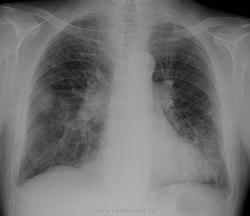

Случай  1.   М., 74 года с сотрясением головного мозга, вестибулопатия. Легочных жалоб нет.  Внимание обращают средние легочные поля с двух сторон. Что-то не нравится, но толком не пойму что.. Может плевральные наслоения?:

Пока по первому случаю. Подозреваю ограниченный пневматоракс справа ( не могу понять, есть ли сосудистый рисунок паракостально в нижнем поле. Не нравится группа очаговых теней слева и клиновидный позвонок в нижнегрудном отделе.

№1. Скорее всего плевральные дела

В первом случае усилен легочный рисунок в прикорневых зонах, обызвествлены хрящи ребер, но очень напрягает позвонок, указанный NIL - такое чувство, что его что-то "съело", нужен онкопоиск